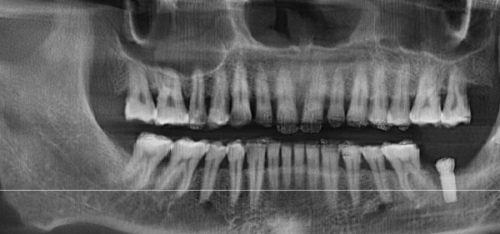

此外,连锁模式下的客源稳定性更高,医生团队和设备的利用率更充分。传统医院可能因患者数量波动导致资源闲置,而中诺口腔通过预约制度和多项目组合,让诊疗资源有效运转,平摊到每位患者的固定成本自然更低。中诺口腔在国内多个城市设立分院,实现设备集中采购、医生团队跨院调配。一台进口CBCT设备,单院采购需200万元,而中诺30家分院分摊后,单院成本降至70万,边际成本压缩。